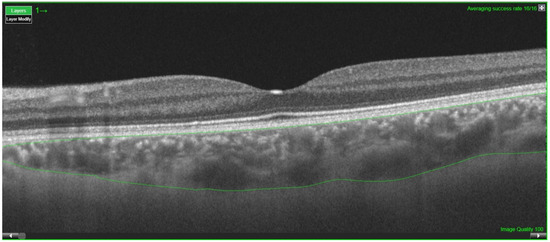

2. Materials and Methods